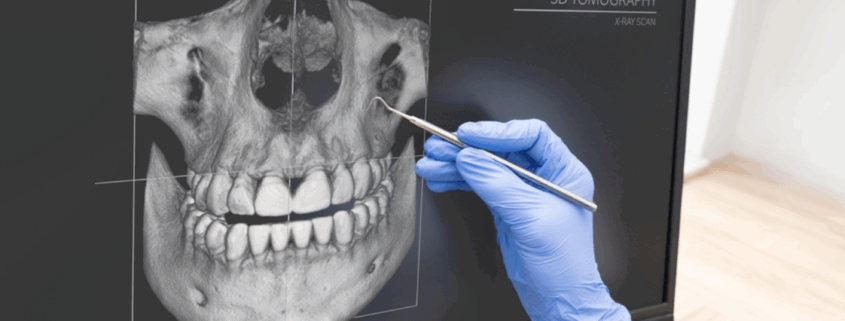

PANORAMIQUE & SCANNER 3D : EXAMENS INDISPENSABLES

Le panoramique et surtout le scanner 3D (CBCT) sont essentiels en implantologie, chirurgie buccale et parodontologie pour planifier les traitements avec précision et sécurité.

2. Le scanner 3D (CBCT)

Ce qu’il montre :

épaisseur et hauteur osseuse,

position du nerf inférieur,

sinus maxillaire,

inclinaison des racines,

trajectoires implantaire optimales.

Le praticien analyse les images en 3D et vous les explique en consultation pour une totale transparence.